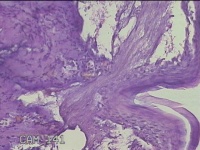

肛周外痔

性别

男

年龄

34岁

临床诊断

1.出血性内痔 2.混合痔 3.肛乳头肥大

一般病史

间断便血3年余。

标本名称

大体所见

灰白暗红色包块0.7x0.3x0.2cm一个,表面糜烂。

图1

像痔。

有可能是外痔。猜的。